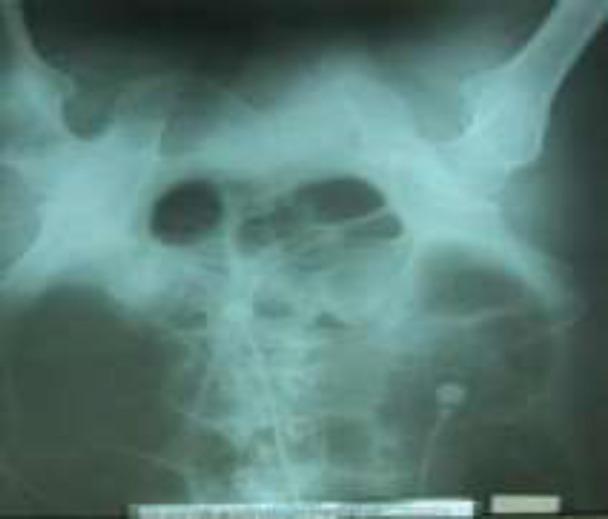

We report the case of a 57-year -old opium male addict, who was. Admitted for abdominal pain, nausea, and vomiting five days after off-pump coronary artery bypass surgery (OPCAB). An abdominal x-ray reported a colonic volvulus. Exploratory laparotomy showed acute abdomen resulting from a gangrene of long segment of splenic flexure caused by volvulus.

我们报告一例57岁男性阿片类药物成瘾者,在非体外循环冠状动脉搭桥手术(OPCAB)后5天因腹痛、恶心和呕吐入院。腹部X线检查报告为结肠扭转。剖腹探查显示为因扭转导致脾曲长段坏疽引起的急腹症。